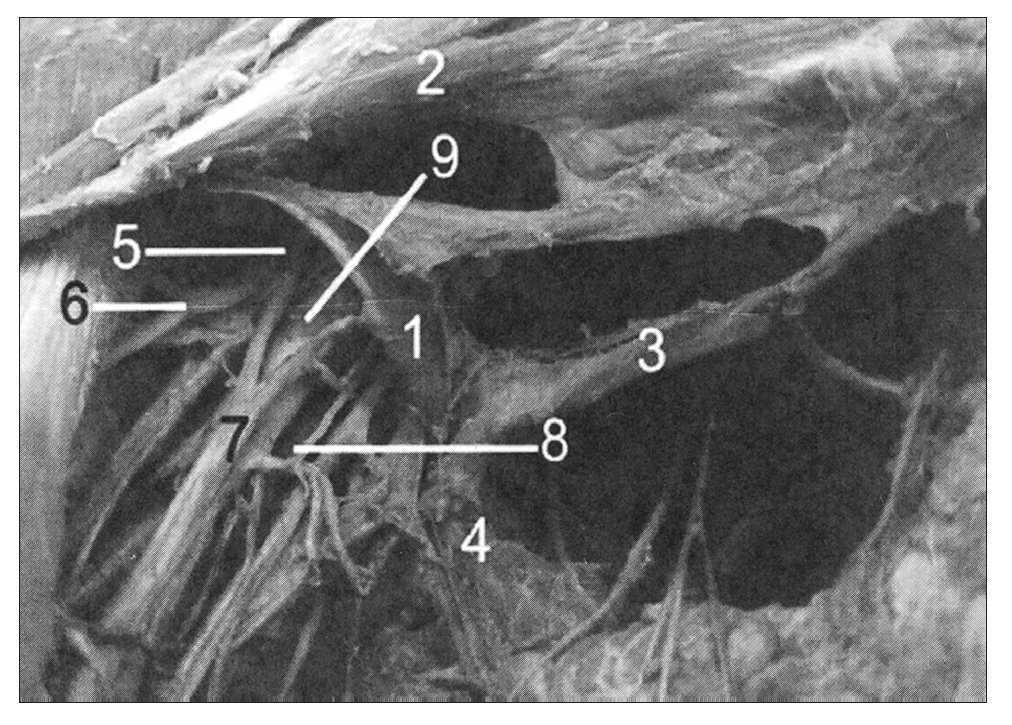

Figura 1. Arco axilar de Langer del lado derecho disecado que cruza el haz neurovascular axilar: 1: arco axilar de Langer; 2: pectoral mayor; 3: pectoralis quartus (variación muscular); 4: latísimo del dorso; 5: cordón lateral del plexo braquial; 6: nervio músculo cutáneo; 7: nervio mediano; 8: nervio cubital; 9: arteria axilar.